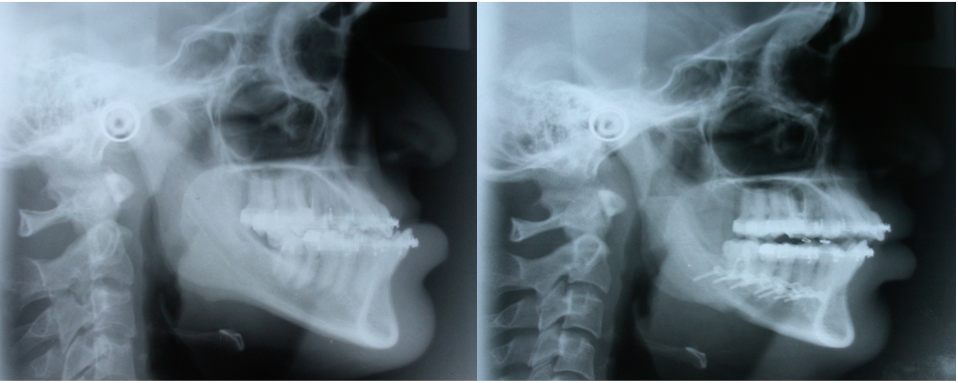

Corrective Jaw Surgery / Orthognathic Surgery

Corrective jaw surgery is aimed at correcting the dentofacial disharmonies through combination of surgery of upper and lower jaws and orthodontics.

Basic goals of this surgery are to provide normal mastication, Speech, Oral function and respiratory function, facial harmony and balance.

After growth completion this surgery can be accomplished at any time presurgical and postsurgical orthodontics are part of complete treatment. Surgery is performed under general anaethesia with all the preoperative evaluations and pictures.

Recovery period is usually smooth and safe, although there can be some complications as is with any other surgery, but can be taken care off. Procedure is safe and very effective results.